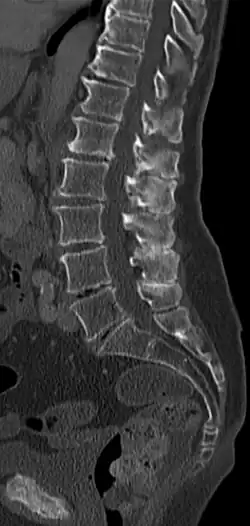

Morbus Baastrup, nach Christian Ingerslev Baastrup auch Baastrup-Syndrom oder Baastrup-Zeichen genannt, ist eine Bezeichnung für Rückenschmerzen infolge sich berührender Dornfortsätze (Processus spinosus) und Irritation der umgebenden Weichteile (Bänder und Muskeln). Im englischen Sprachraum wird die Erkrankung daher auch passend „kissing spine disease“ genannt.

- Radiologisch: Radiologisch nachgewiesene Berührung von Dornfortsätzen, hauptsächlich im Bereich der Lendenwirbelsäule infolge verstärkter Lordosierung und meist verschleißbedingter Verschmälerung der Bandscheiben mit Ausbildung reaktiver Sklerosen und Nearthrosen. Funktionsaufnahmen in Reklination zeigen eventuell den direkten Kontakt betroffener Dornfortsätze.